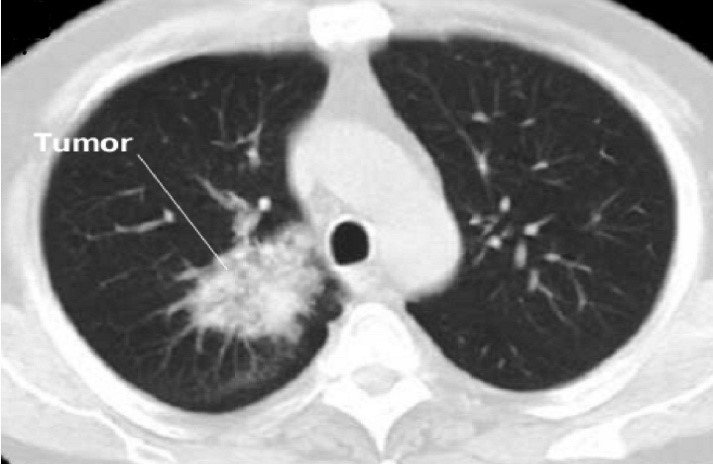

- Görüntüləmə əlamətlərinə rentgenoloji və KT müayinələrində ağciyərdə kütlə (kütlələr), bronxoskopiyada bronxial kütlənin görünməsini, USM və KT-də qaraciyərdə, sümüklərdə, böyrəküstü vəzidə və beyində kütlələrin tapılmasını aid etmək olar.

- Mediastinal strukturlara yayılmanı dəqiqləşdirmək üçün KT və endobronxial USM ilk seçimdir (Şəkil 11).

Şəkil 11. Ağciyər xərçənginin diaqnostikası (KT).